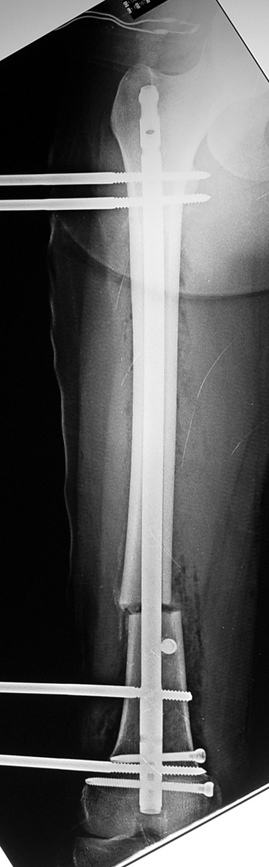

Installment of the intramedullary nail and osteotomy:

The patient lies is supine position at a traction table and legs are crossed with the uninvolved leg at the bottom. The medullary cavity is penetrated through piriform fossa using the standard method, and medulla is reamed 1.5 mm thicker than the nail to be used, over a guidewire. Proximal femur is reamed more, because the intramedullary nail is thicker proximally. The osteotomy site is planned at the X-Rays. It is important that at least 8 cm. of nail remains distal to the osteotomy site after the completion of the lengthening procedure. Percutaneous corticotomy is performed. The guide wire is advanced distally in order to measure the length of the nail. An intramedullary nail of apropriate length is placed. In the end, the nail is interlocked proximally, a suction drain is placed and the fist step of the operation is completed.

2. Step:

The application of the external fixator: Three Schanz screws are placed distally and three screws are placed proximally. At least 1 mm of distance shall remain between the screws and the nail.

In selected cases, we prefer to use a combination of a unilateral dynamic axial fixator and an interlocked intramedullary nail, in order to protect the length and alignment after the completion of the lengthening procedure. As a prerequisite for this technique, the narowest diameter of the medullary cavity shall be wider than 7 mm and the length of the nail segment distal to the osteotomy site shall be at least 8 cm. after the completion of the lengthening procedure.The intramedullary nail neutralizes shear and bending forces on femur during lengthening, shortens external fixation time, and protects newly formed bone against fractures. In our series, subtrochanteric osteotomy was performed in one case. No varus angulation occured despite the intramedullary nail.